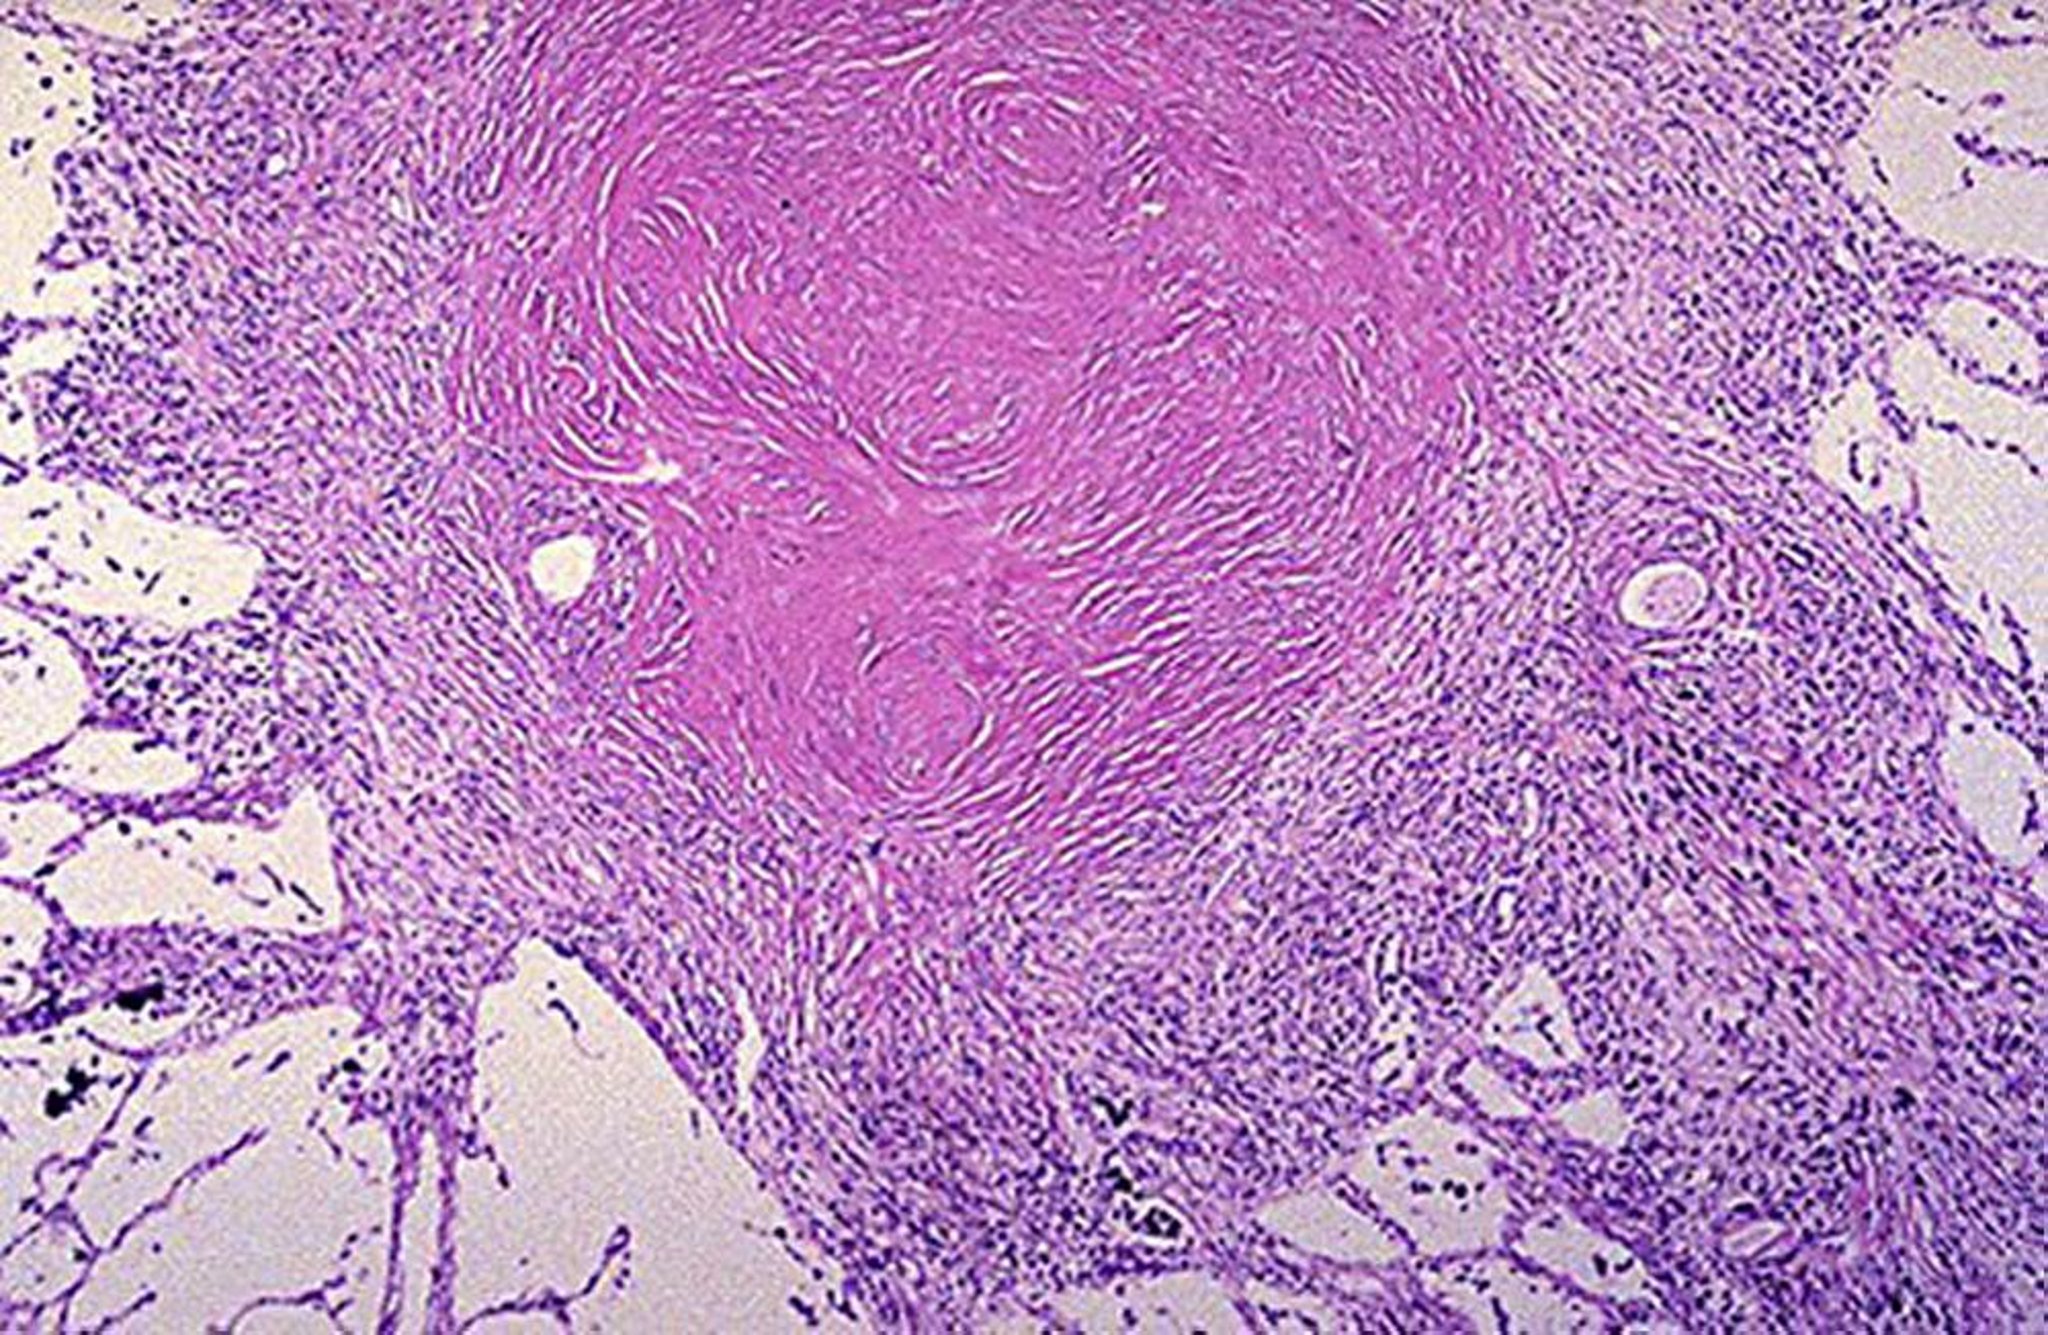

Silica-laden macrophages promote the formation of the pathognomonic silicotic nodule in the lung. These nodules initially contain collagen fibers and scattered birefringent particles of silica that are best seen with polarized light microscopy. As they mature, centrally arranged collagen fibers are surrounded by an outer layer of inflammatory cells.

In low-intensity or short-term exposures, these nodules remain discrete and do not compromise lung function (simple chronic silicosis). With higher-intensity or more prolonged exposures (complicated chronic silicosis), these nodules coalesce and cause progressive fibrosis and restrictive lung dysfunction, or they sometimes form large conglomerate masses (called progressive massive fibrosis).